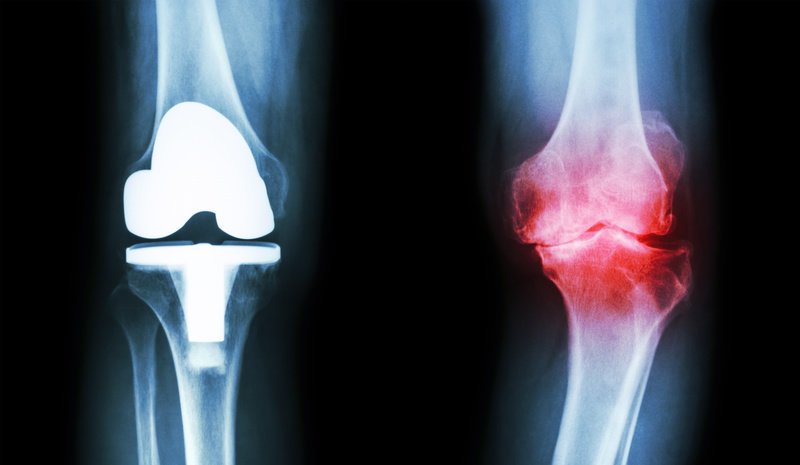

Zwyrodnienie stawu kolanowego, czyli gonartroza jest częstą przyczyną bólu kolana. Choroba ta stopniowo uszkadza staw, co może w końcu prowadzić do konieczności jego wymiany na metalową protezę. Aby dłużej cieszyć się swoim własnym kolanem lub nawet uniknąć operacji należy odpowiednio wcześnie zastosować nowoczesną terapię.

Natomiast w przypadku bardzo ciężkich i nieodwracalnych uszkodzeń kolana, w których wszczepienie endoprotezy jest konieczne, dobrze dobrane leczenie pozwala znacznie zwiększyć komfort podczas oczekiwania na operację.

Do postawienia diagnozy najczęściej wystarczają zdjęcia rentgenowskie stawu kolanowego. W niektórych przypadkach lekarz może zlecić rezonans magnetyczny lub artroskopię. U części pacjentów wykonuje się badania laboratoryjne takie jak czynnik reumatoidalny, poziom kwasu moczowego, OB, CRP i morfologia krwi obwodowej.

Leczenie operacyjne

Jeżeli zmiany zwyrodnieniowe doprowadzą do ciężkiego i nieodwracalnego uszkodzenia stawu przeprowadza się operację wymiany stawu na sztuczny, czyli wszczepienia endoprotezy stawu kolanowego.

W wielu przypadkach konieczność wymiany stawu można odłożyć w czasie lub nawet jej uniknąć, jeżeli odpowiednio wcześnie rozpocznie się leczenie mające na celu ochronę chrząstki.